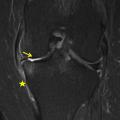

Gonarthrose post traumatique

GONARTHROSE

Image